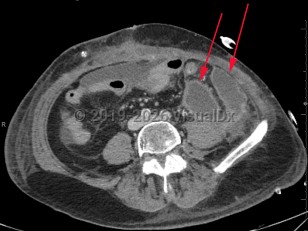

Intraabdominal abscess

A collection of pus located inside the abdominal cavity that forms as a result of inoculation of one or more pathogens into a normally sterile intraabdominal location.

The clinical presentation is varied and depends on the location of the abscess in the intraabdominal cavity. Vague abdominal discomfort is common, and pain may localize to a site of intraabdominal inflammation (in the patient with diverticulitis, for example). Fever and leukocytosis are also seen. The clinician should be mindful that patients who are immunosuppressed may have very mild and nonspecific symptoms. Patients who have a spinal cord injury or altered mental status may be similarly difficult to diagnose.

Patients who suffer from diverticulitis, inflammatory bowel disease (eg, ulcerative colitis, Crohn disease), or conditions that may lead to intestinal obstruction and subsequent perforation are at risk for intraabdominal abscesses. Also, patients who have penetrating trauma to the abdomen or undergo a surgical procedure involving intraabdominal or pelvic organs are at risk for this condition.